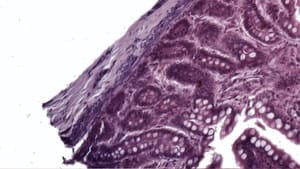

Level Clipping Filter — Before